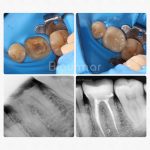

Casos reales de antes y después

Cada sonrisa tiene una historia. En Clínica Dental Blaumar te mostramos casos reales de pacientes que confiaron en nosotros para mejorar su salud y su estética dental. Antes y después, procesos y resultados explicados con claridad, para que veas cómo trabajamos: con planificación, precisión y un trato cercano de principio a fin.